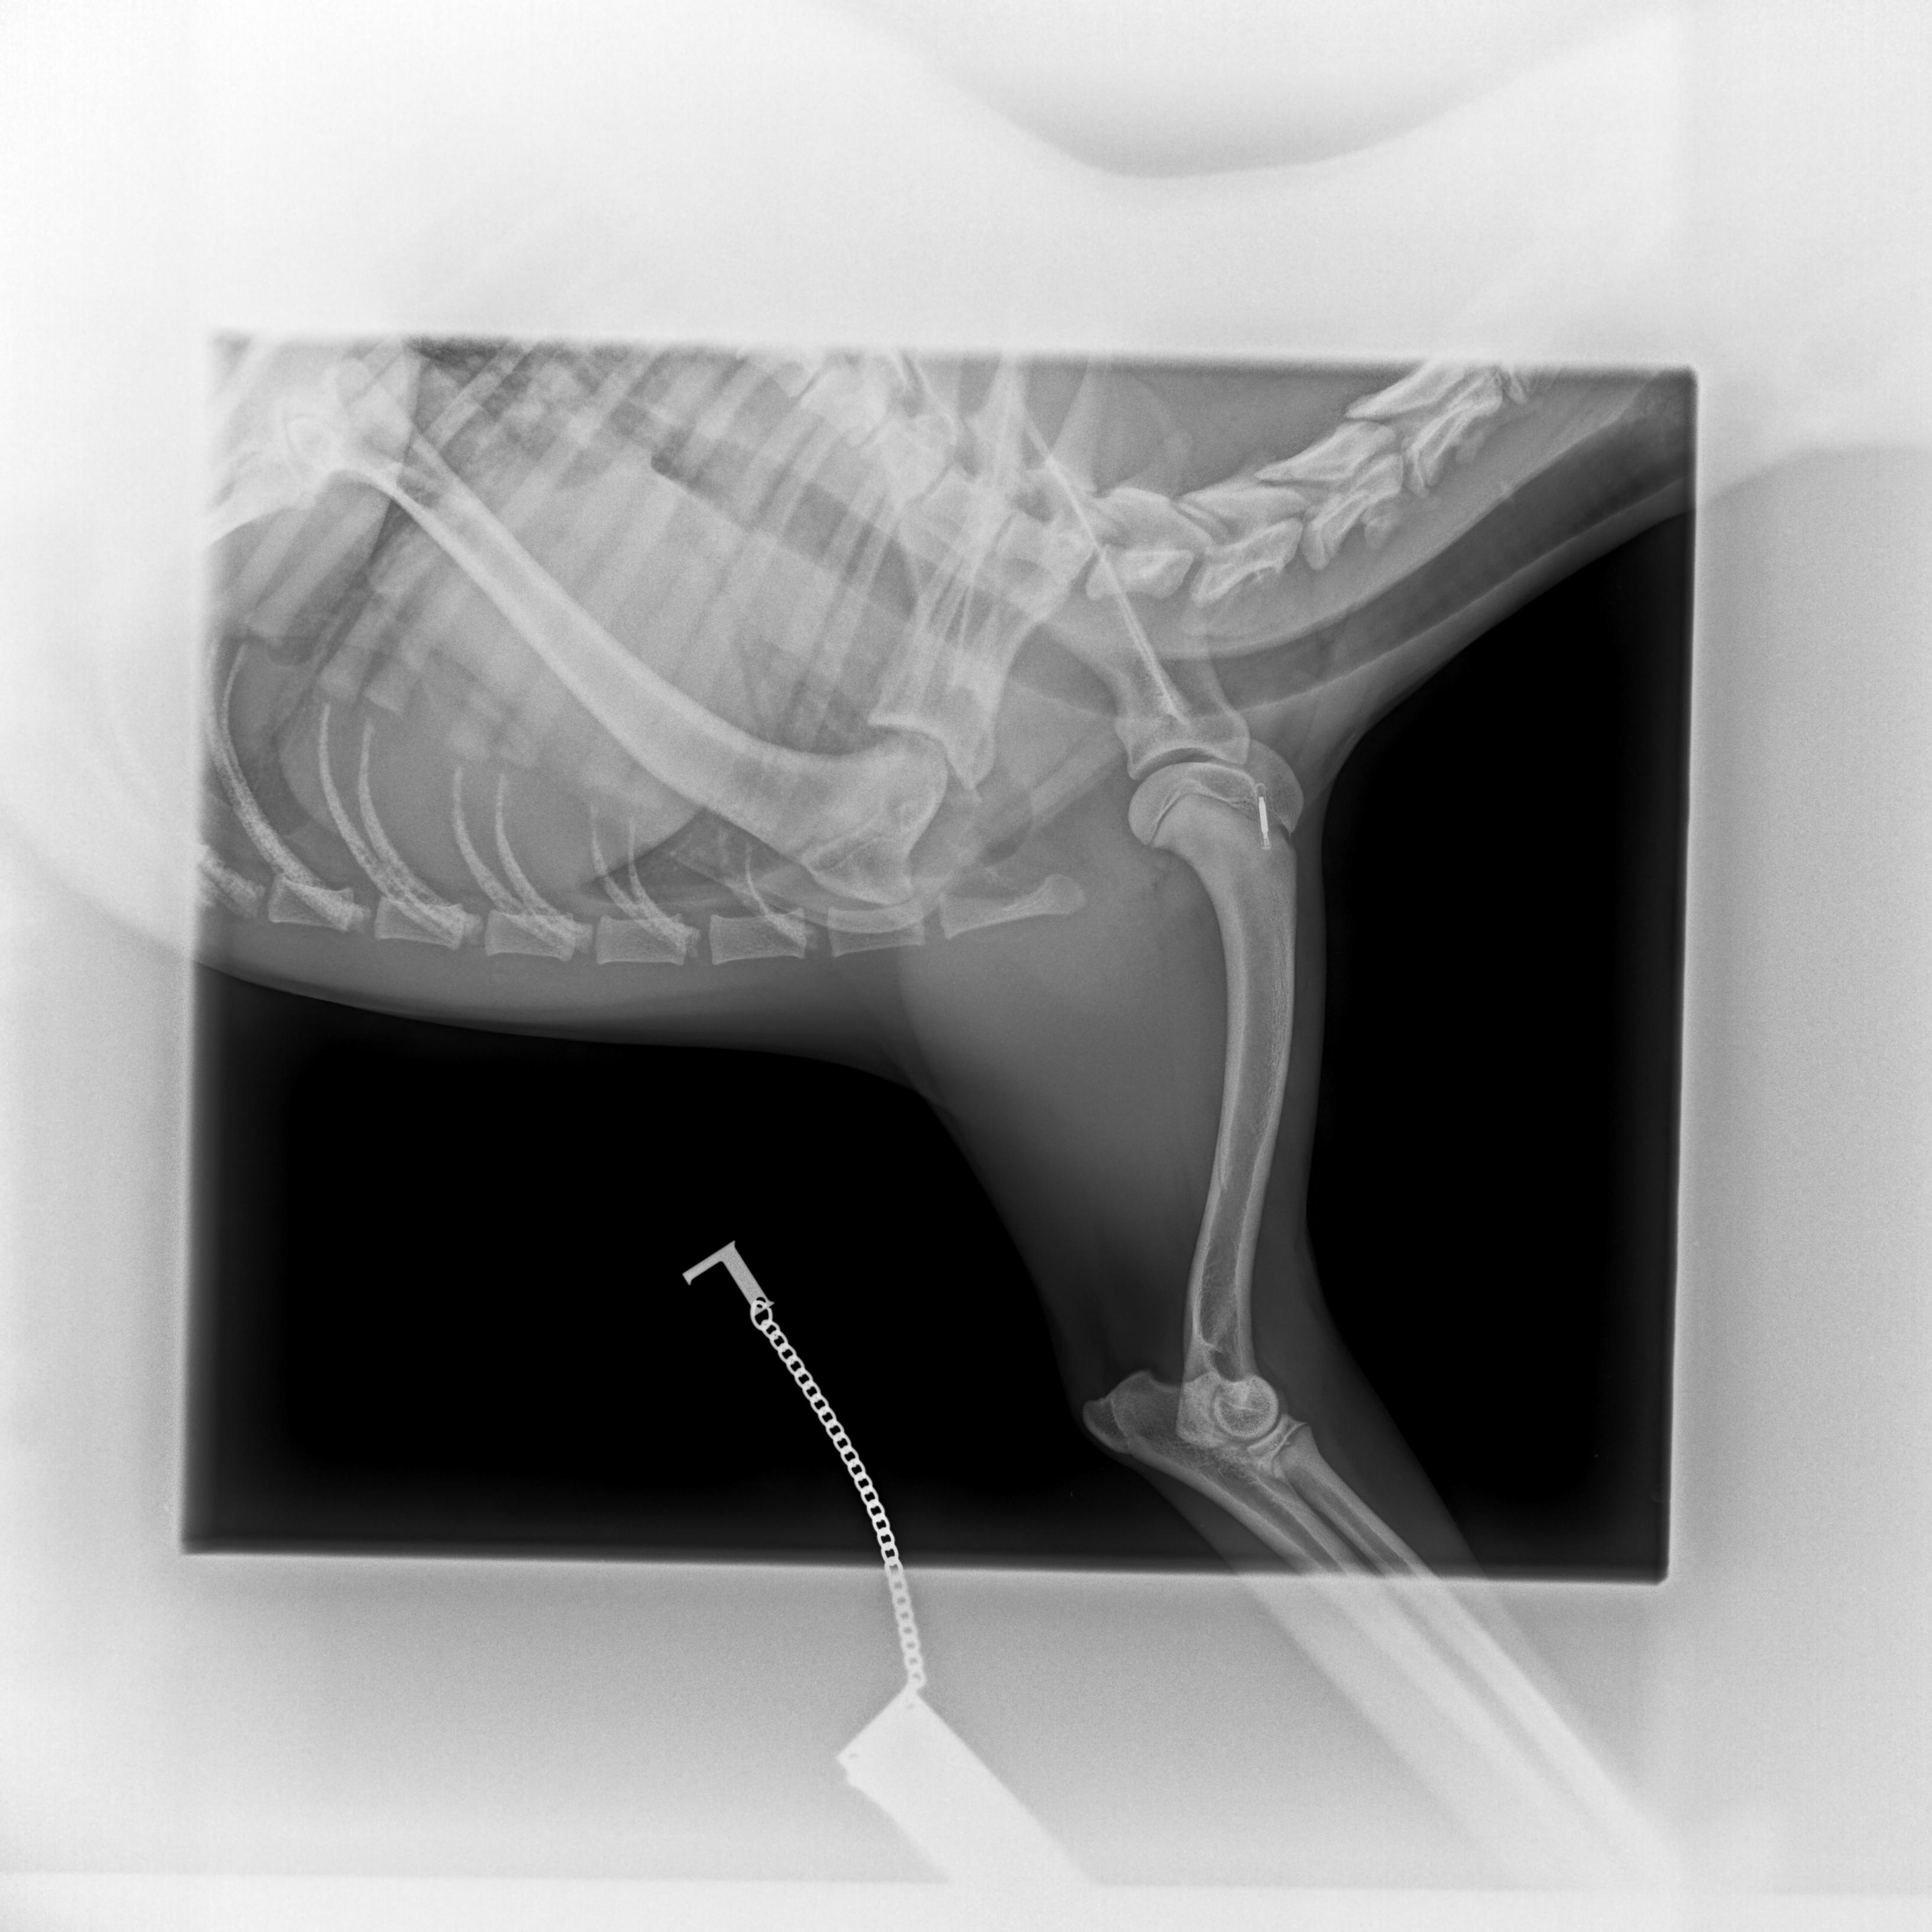

Cushingův syndrom, taktéž nazývaný Hyperadrenokorticismus, patří v současnosti spolu s diabetes mellitus mezi nejčastěji se vyskytující endokrinologická onemocnění psů. Způsobuje ho nadbytek glukokortikoidů, jako Cushingův syndrom pak označujeme soubor příznaků, které onemocnění doprovázejí.